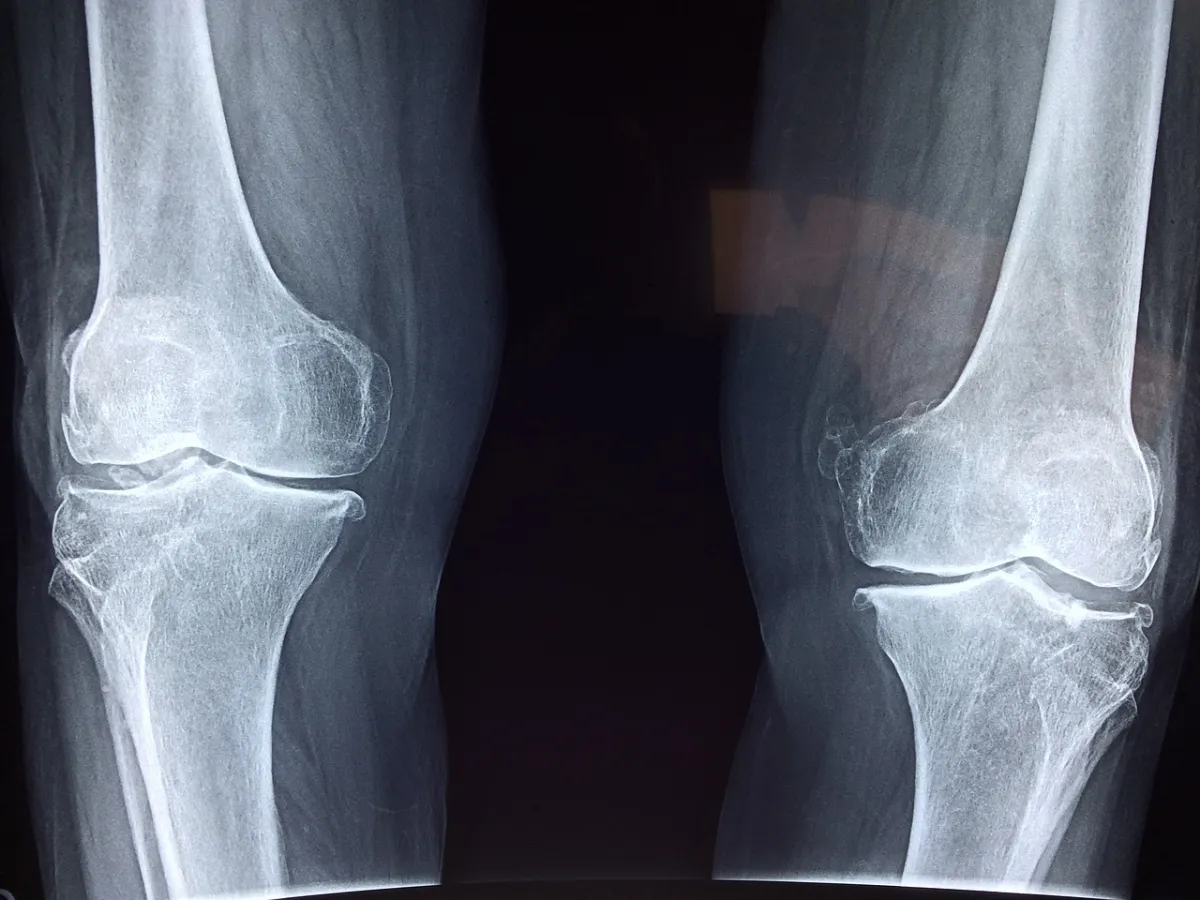

휜다리 어떻게 교정할 수 있을까?|X자 다리 외반슬, O자 다리 내반슬

외반슬은 X자 다리라고 부르며, 내반슬은 O자 다리라고 부릅니다.

외반슬과 내반슬을 구분하는 방법

외반슬

X자 다리라고도 부르며, 외관상 무릎은 안쪽으로 모이고, 무릎 아래부터는 바깥쪽으로 벌어지는 X자 모양을 나타내기 때문에 X자 다리라고 칭합니다.

스쿼트 동작을 했을 때 무릎이 내회전 한다면 외반슬입니다.

내반슬

O자 다리의 경우 외관상 무릎은 바깥쪽으로 벌어지며, 무릎 아래부터는 안쪽으로 휘어지는 O자 모양을 나타내기 때문에 O자 다리라고 칭합니다.

대표적인 특징으로는 8 자 걸음걸이가 있으며, 스쿼트 동작시 무릎이 외회전 한다면 내반슬입니다.

복합형

XO자 다리라고도 부르는 외반슬과 내반슬의 특징을 모두 갖고 있는 경우입니다.